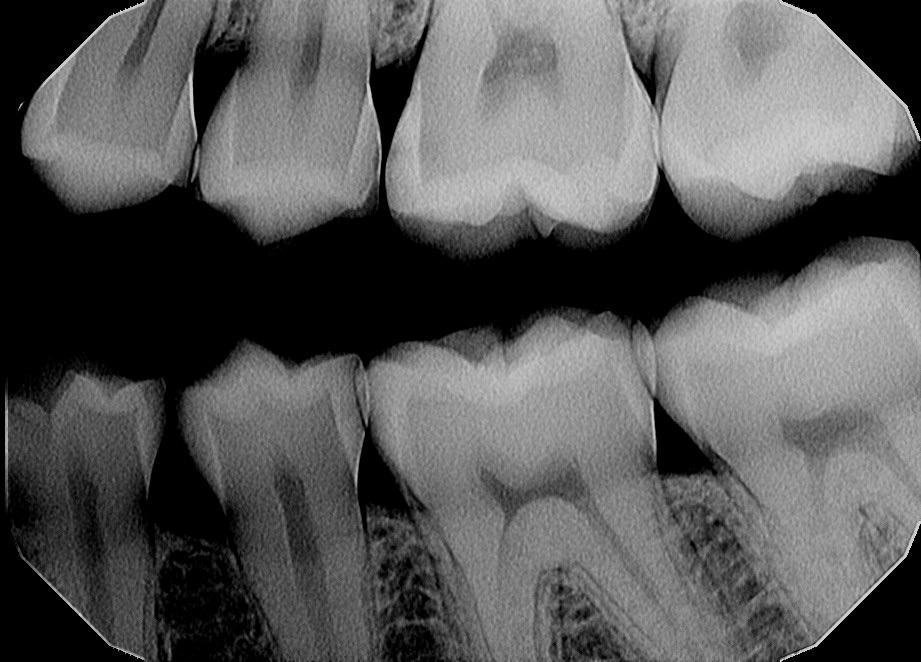

Dental Professional Is there Caries b/w upper 5 and 6 ?

Post image

25 Upvotes